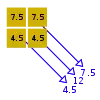

- A basic premise in back-projection is that any attenuation of the X-ray beam has occurred uniformly along the path followed from the source to the detector. Let's consider a simple tomographic slice containing just four voxels to illustrate the computational approach - see Figure 7.11. The first projection, P1 is obtained from a horizontal exposure from left to right in the figure. The back-projection of P1 involves putting the values 7 and 9 in both elements of the first and second rows, respectively. The second projection, P2 adds a 4 to the top right element, 1 to the bottom left element and 11 to the other two elements when it is back-projected. The other projections are treated in a similar fashion. Following regularisation of the data set the final image is obtained at the bottom left of the figure.